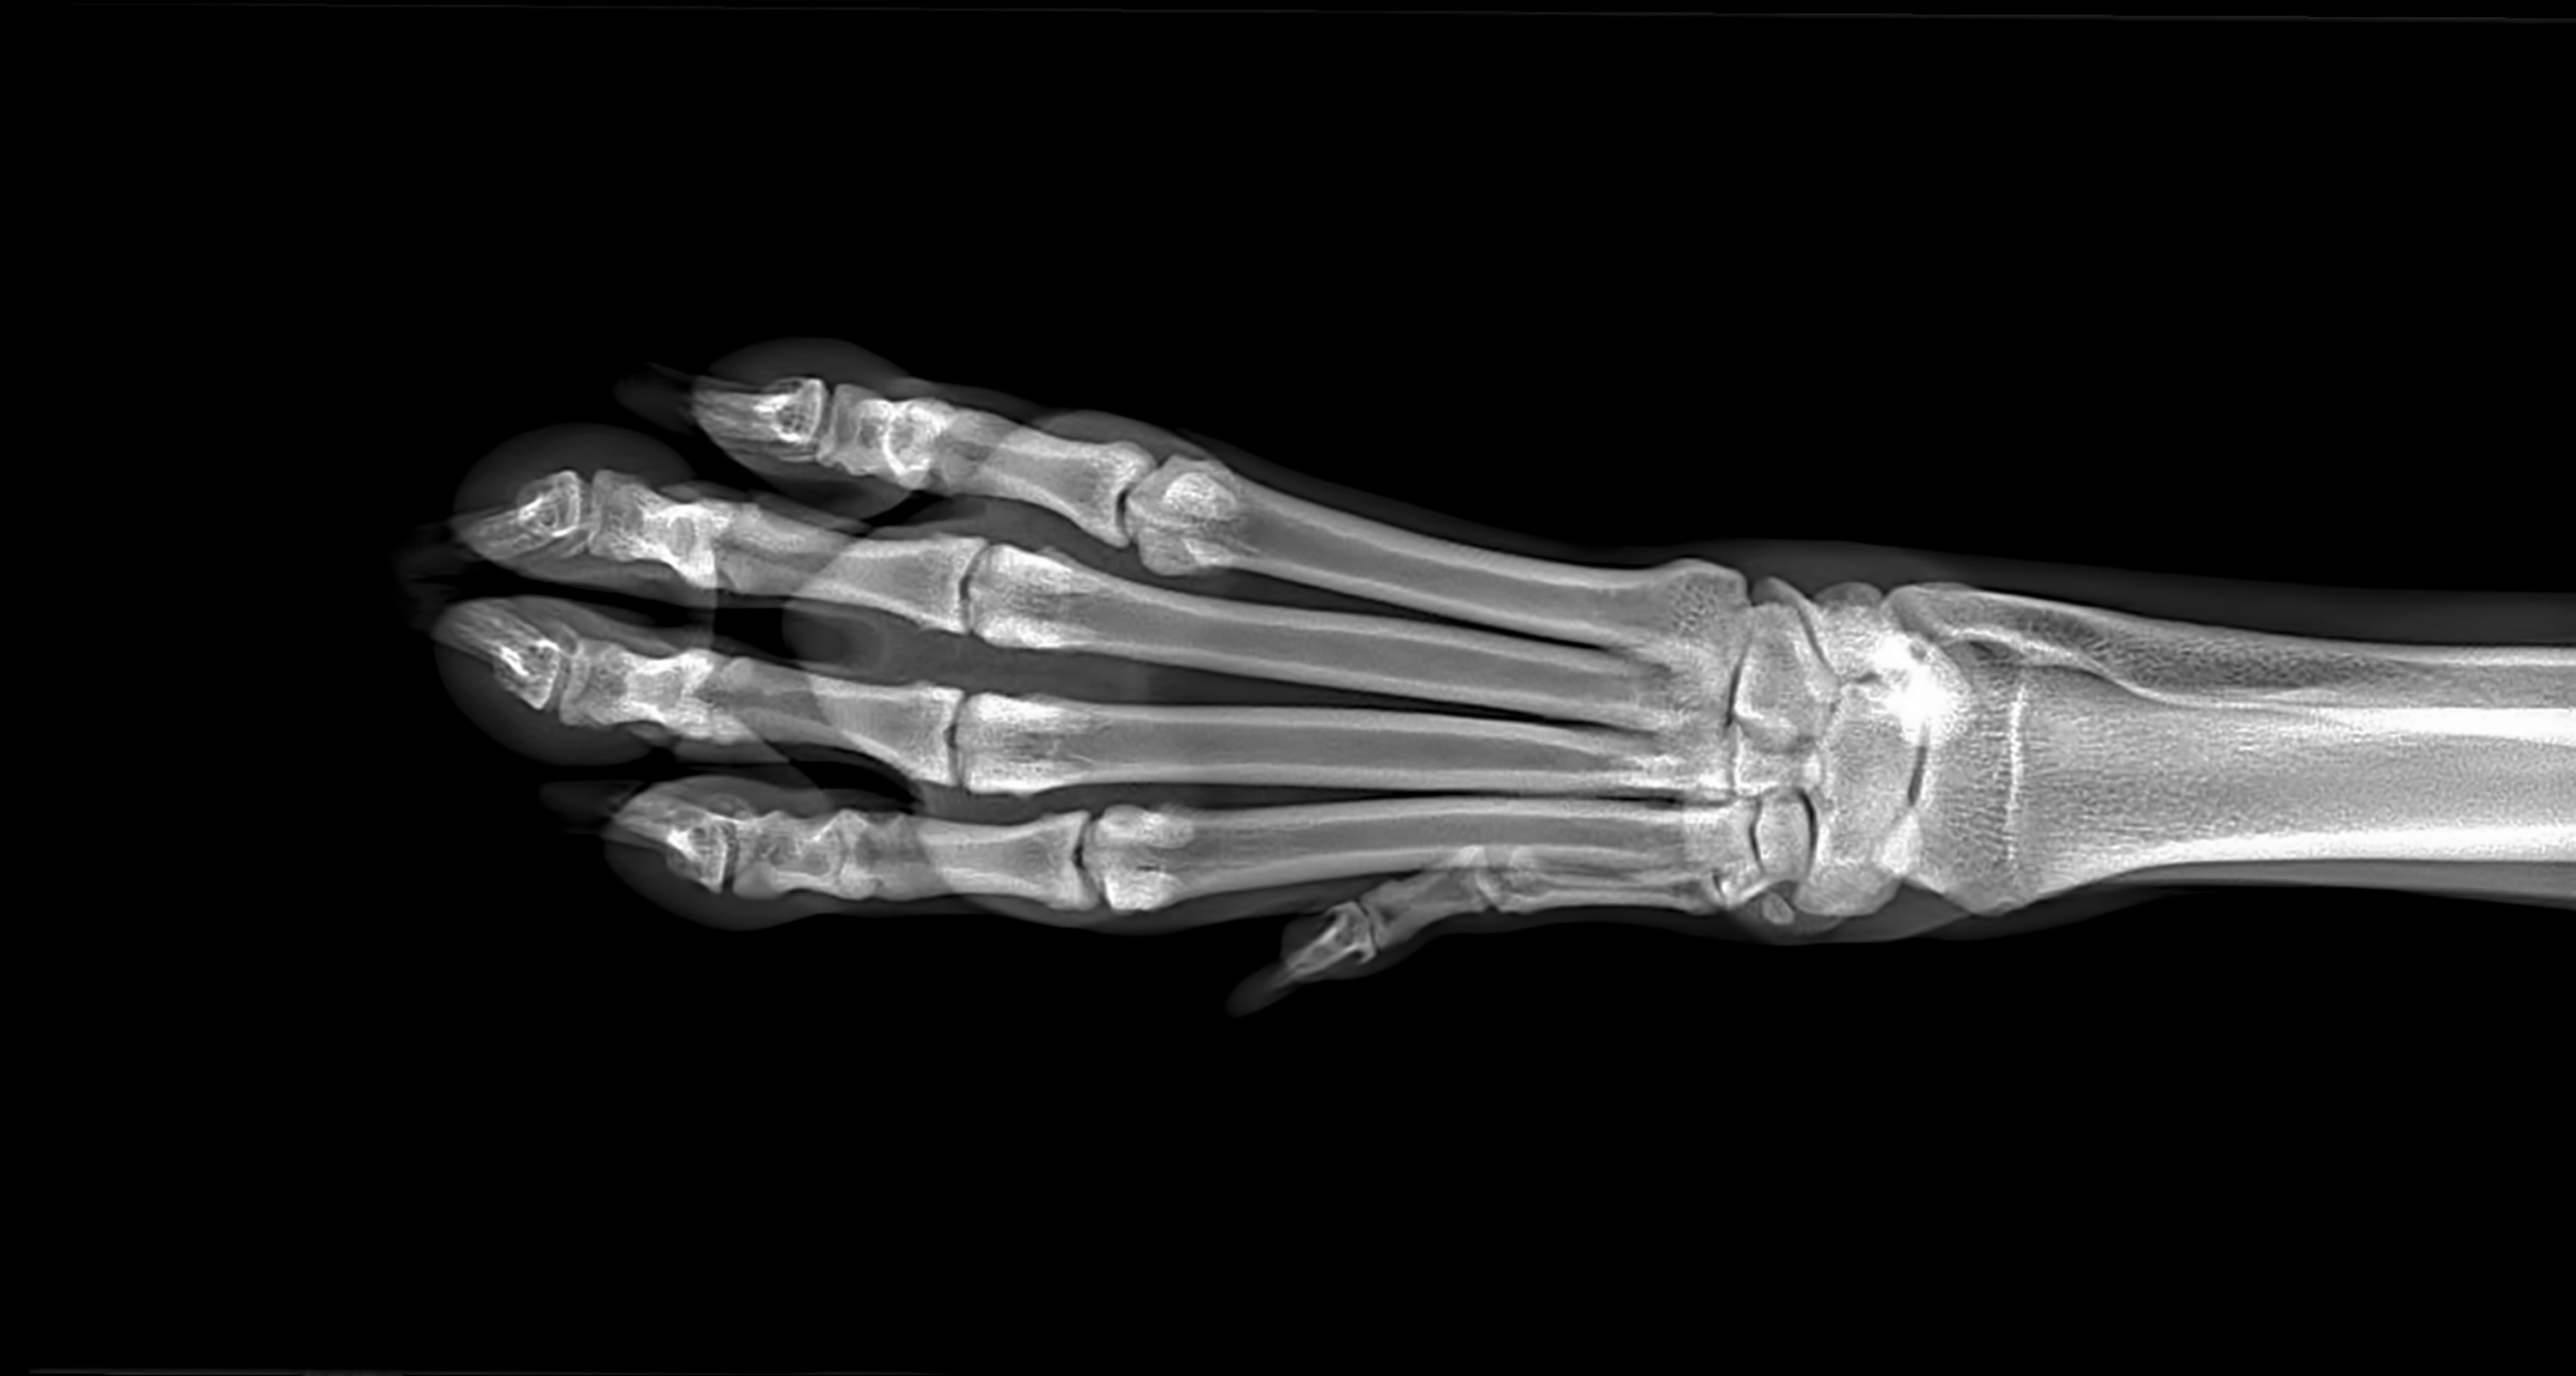

This exhibit will showcase the work that we have done to test 3D printed bones. This project is a continuation of P20061: Creating Bone Replicas for Surgical Planning. The previous project determined a list of viable materials to use as a base for 3D printed bone samples. The customer of this project is Will Byron, representing MedDimensions LLC. The objective of this project is to take the 3D printed bone samples and determine a test protocol that will determine if the 3D printed bones accurately simulate the tactile sensation of real bone based on comparing outputted data. It is also a goal to create a test fixture that can provide a reproducible method for testing other 3D printed bones.